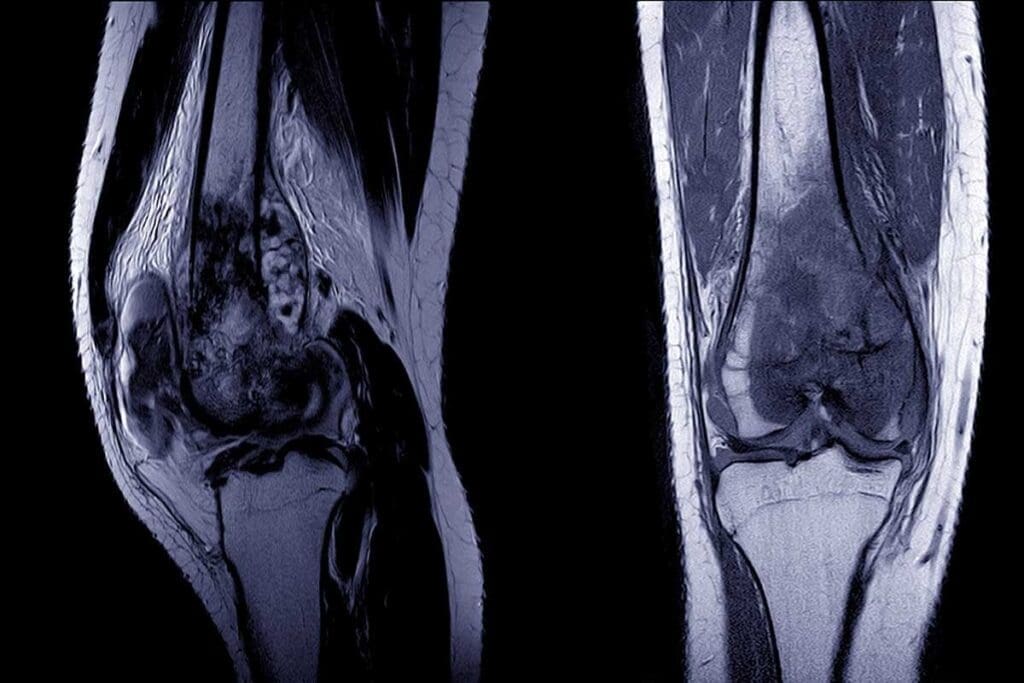

Imaging Studies

Imaging tests are vital for diagnosing Ewing sarcoma. They show where, how big, and how far the tumor is.

Common imaging studies used include:

- X-rays

- MRI (Magnetic Resonance Imaging) scans

- CT (Computed Tomography) scans

- PET (Positron Emission Tomography) scans